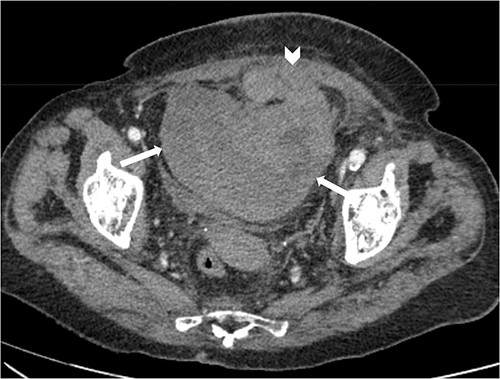

Suspecting internal haemorrhage, contrast-enhanced computed tomography (CECT) of the abdomen and pelvis was arranged. The CT images showed the presence of multiple haematomas with evidence of active bleeding (Figs 1 and 2).

Axial non-contrast CT abdomen and pelvis at the level of acetabulum. Rectus sheath haematoma (chevron) that appears to have dissected through the rectus sheath into the extraperitoneal pelvic space (arrows).